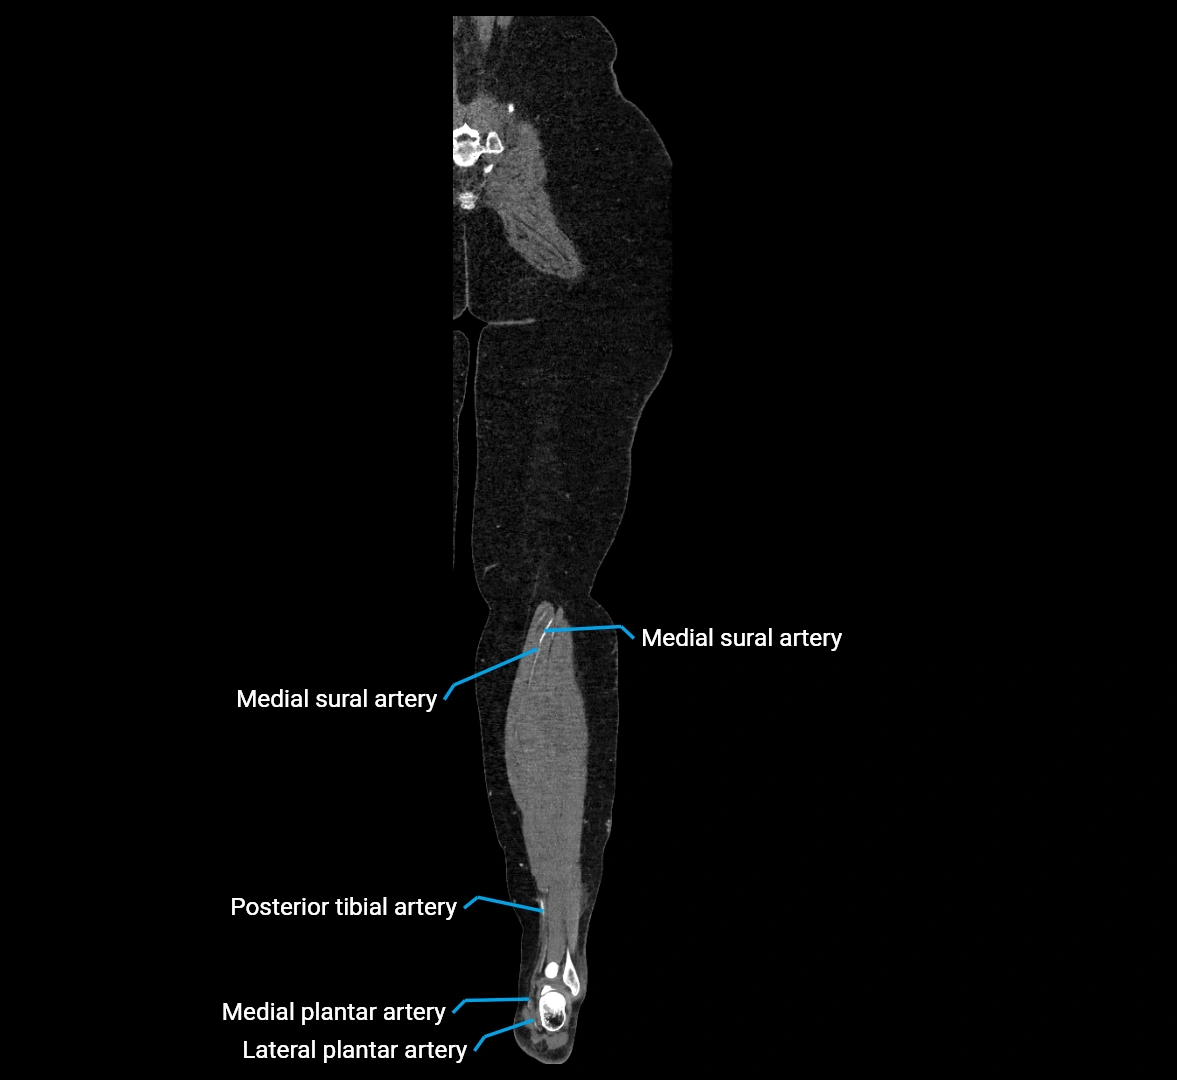

Contrast-enhanced CT (CTA):

• Gold standard for abdominal aortic imaging

• Provides excellent detail of lumen, wall, aneurysm, thrombus, and branch vessels

• Multiplanar and 3D reconstructions help in aneurysm measurement, stent graft planning, and dissection evaluation

• Detects acute rupture, traumatic injury, or occlusion with high sensitivity